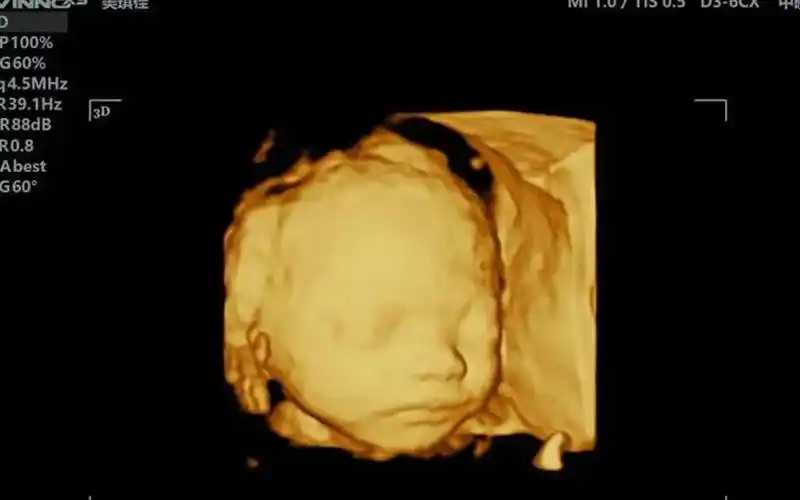

做四维彩超宝宝正脸像妈妈是不是生女孩几率高